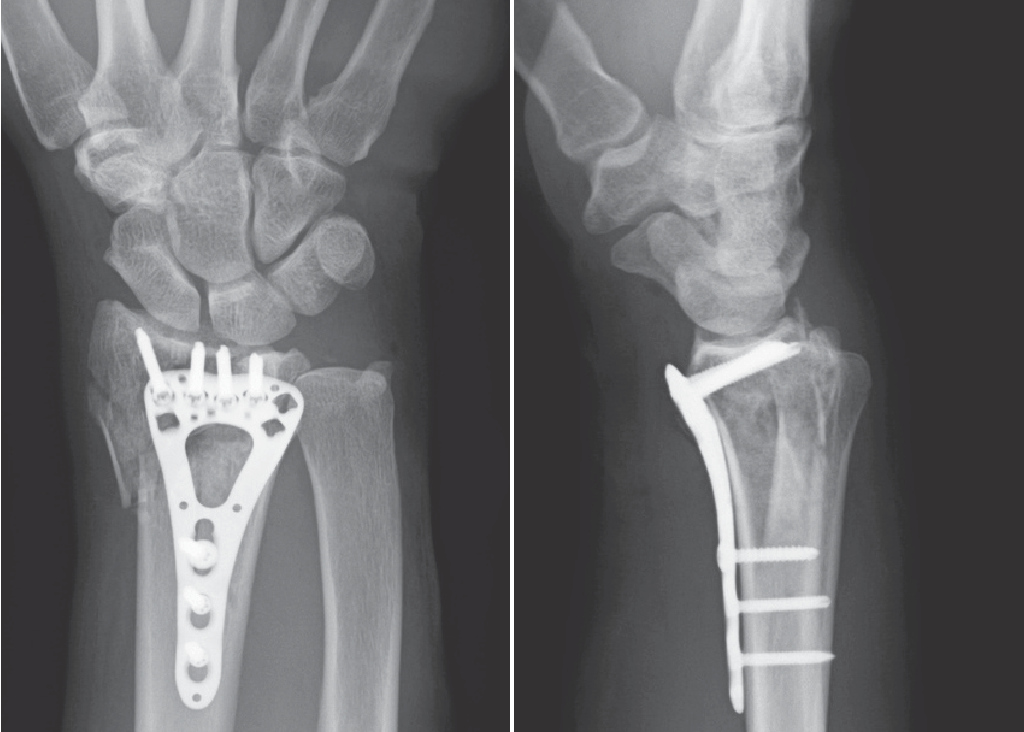

2023-07-06 Dans le domaine de la chirurgie orthopédique, le développement et l'évolution de diverses techniques et dispositifs chirurgicaux ont grandement contribué à l'amélioration des résultats pour les patients.L'une de ces avancées est la plaque de verrouillage, un implant orthopédique spécialisé utilisé pour la fixation des fractures et des déformations osseuses.E